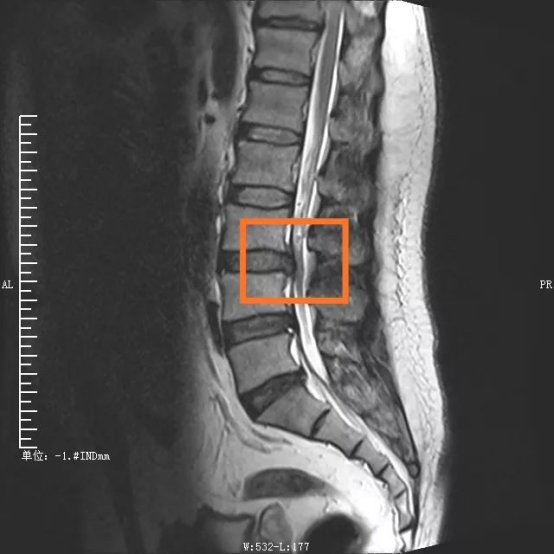

手術(shù)部位術(shù)前/術(shù)后對比圖

“如果說傳統(tǒng)開放性腰椎手術(shù)走的是一條‘大刀闊斧’的路,那么OLIF則是走巧妙的創(chuàng)新之路?!敝鞯夺t(yī)生鄧?yán)祝ㄖ貞c市醫(yī)學(xué)會神經(jīng)脊柱學(xué)組副組長)說道,患者陳先生被腰痛纏繞1年多,近段時間嚴(yán)重到走路都困難,經(jīng)檢查發(fā)現(xiàn)腰3/4椎間盤突出、腰椎管狹窄,屬于典型的腰椎疾病。

“OLIF手術(shù)采用側(cè)方入路,手術(shù)區(qū)域在椎管前方,不破壞后方結(jié)構(gòu),不分離脊柱后方肌肉,極大地減少了組織損傷?!编?yán)捉榻B,這種技術(shù)巧妙在于,充分了利用腹膜后主動脈與腰大肌前緣之間的自然間隙,到達目標(biāo)椎體斜外側(cè),結(jié)合神經(jīng)外科顯微手術(shù)技術(shù),切除病變椎間盤,實現(xiàn)椎間融合。若手術(shù)順利,術(shù)中患者出血僅20ml左右,患者術(shù)后2天就能下床活動,3天即可出院。